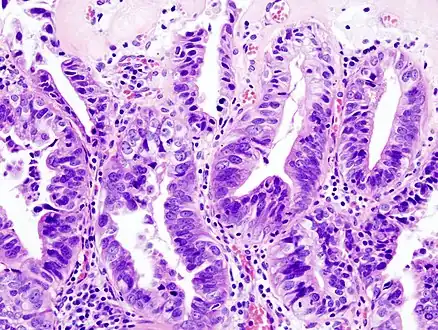

Gallbladder adenocarcinoma lymphatic invasion histopathology

Gallbladder adenocarcinoma histopathology